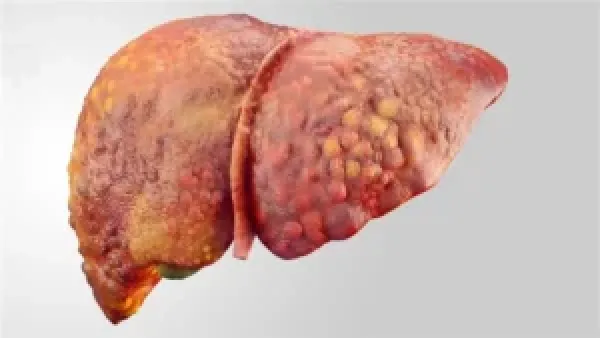

النظام الغذائي بدون سكر ولحوم وألبان وخبز أصبح اتجاهًا شائعًا لدى الكثيرين الباحثين عن أسلوب حياة يجمع بين الرشاقة والصحة الجيدة وراحة الجهاز الهضمي؛ حيث يتج...